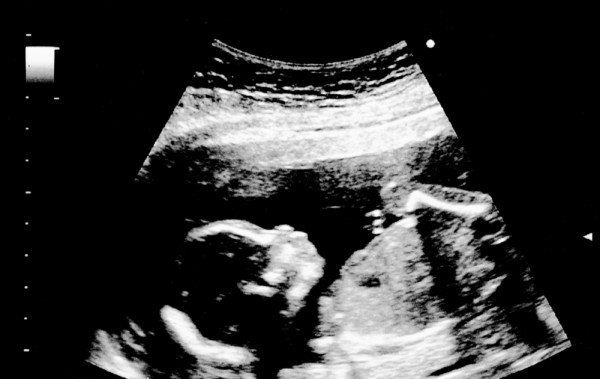

УЗИ

Ультразвуковое исследование на восемнадцатой неделе беременности проводится в рамках второго скринингового обследования. Специалист оценивает не только размеры плода, такие как рост и вес, но и другие важные параметры:

- длину костей (плечевой, бедренной, голени и предплечья);

- диаметр живота и головы;

- расположение внутренних органов;

- структуру мозга и сердца;

- правильность развития ребенка и плаценты;

- объем околоплодных вод.

На этом этапе УЗИ позволяет точно определить пол малыша, так как внешние половые органы у мальчиков и девочек уже хорошо развиты. Кроме ультразвукового исследования, женщине назначаются анализы крови и мочи, а также тесты на два маркера – НЭ и АФП.

На восемнадцатой неделе сердечная мышца плода достаточно развита, что позволяет врачу при ультразвуковом исследовании определить наличие или отсутствие пороков развития.